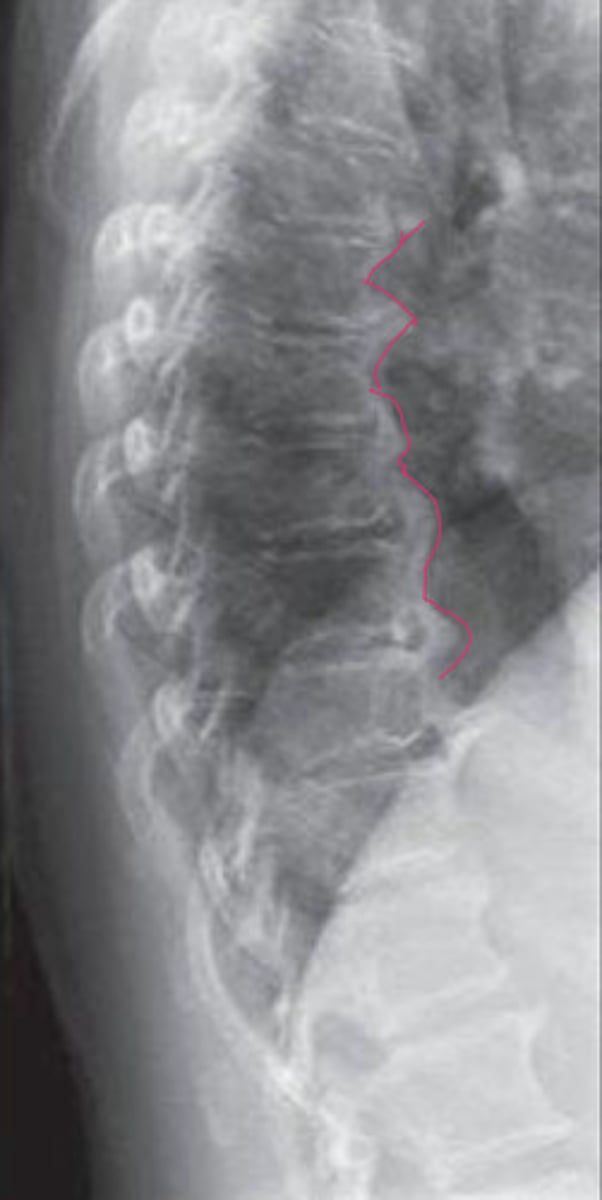

Disc calcification

What is the red

Calcification of the posterior vertebral line

Looks like fracture, not actually

What is the blue?

What is the red?

DISH (mid body flow of the anterior vertebral line)

What is wrong with this image?

Calcification of ALL or DISH

What is the pathology?